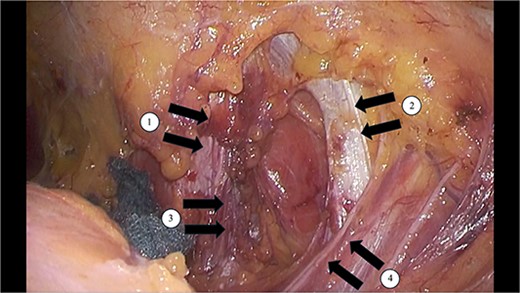

Swelling and tenderness were observed in the left lumbar back area. Abdominal contrast-enhanced CT showed the herniation of the retroperitoneal fat tissue into the abdominal wall was observed dorsally to the left kidney (Fig. 1). Surgery was performed because the pain persisted and there was a possibility of organ incarceration in the future. We used the laparoscopic system to perform the operation. The patient was positioned in the right lateral decubitus position under general anesthesia. A camera was inserted at the umbilicus, and 5 mm ports were placed in the epigastric region and left lower abdomen. The omentum and descending colon were adhered to the abdominal wall and were dissected. The descending colon was dissected laterally along the white line, and the dorsal side of the Gerota’s fascia was dissected. A 3 cm × 2 cm hernia orifice, bordered by the 12th rib lower edge, internal oblique muscle, serratus posterior inferior muscle, and quadratus lumborum muscle, was identified (Fig. 2). Part of the fatty tissue, including Gerota's fascia, was herniated, and it was resected as much as possible. A BARD Ventralight ST 10.2 × 15.2 cm mesh was placed, and it was fixed to the ribs and muscles using the double crown method with AbsorbaTack (Fig. 3). The operative time was 109 minute, with little blood loss. The patient discharged on postoperative Day 2 without postoperative complications. One year has passed since the surgery, and there have been no recurrence of the hernia, neuropathic pain.

A 3 cm × 2 cm hernia orifice, bordered by the ①12th rib lower edge, ②internal oblique muscle, ③serratus posterior inferior muscle, and ④quadratus lumborum muscle, was identified.

A BARD Ventralight ST 10.2 × 15.2 cm mesh was placed, and it was fixed to the ribs and muscles using the double crown method with AbsorbaTack.